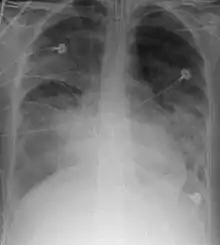

O termo insuficiência respiratória, em medicina, é usado para descrever a troca inadequada de gases pelo sistema respiratório, resultando numa incapacidade de manter os níveis de oxigênio e dióxido de carbono arteriais dentro dos níveis normais. A baixa oxigenação é denominada como hipoxemia e um aumento dos níveis sanguíneos de dióxido de carbono denomina-se hipercapnia.

Pode ser dividida em Insuficiência respiratória aguda e Insuficiência respiratória crônica, dependendo da velocidade de instalação.[1]